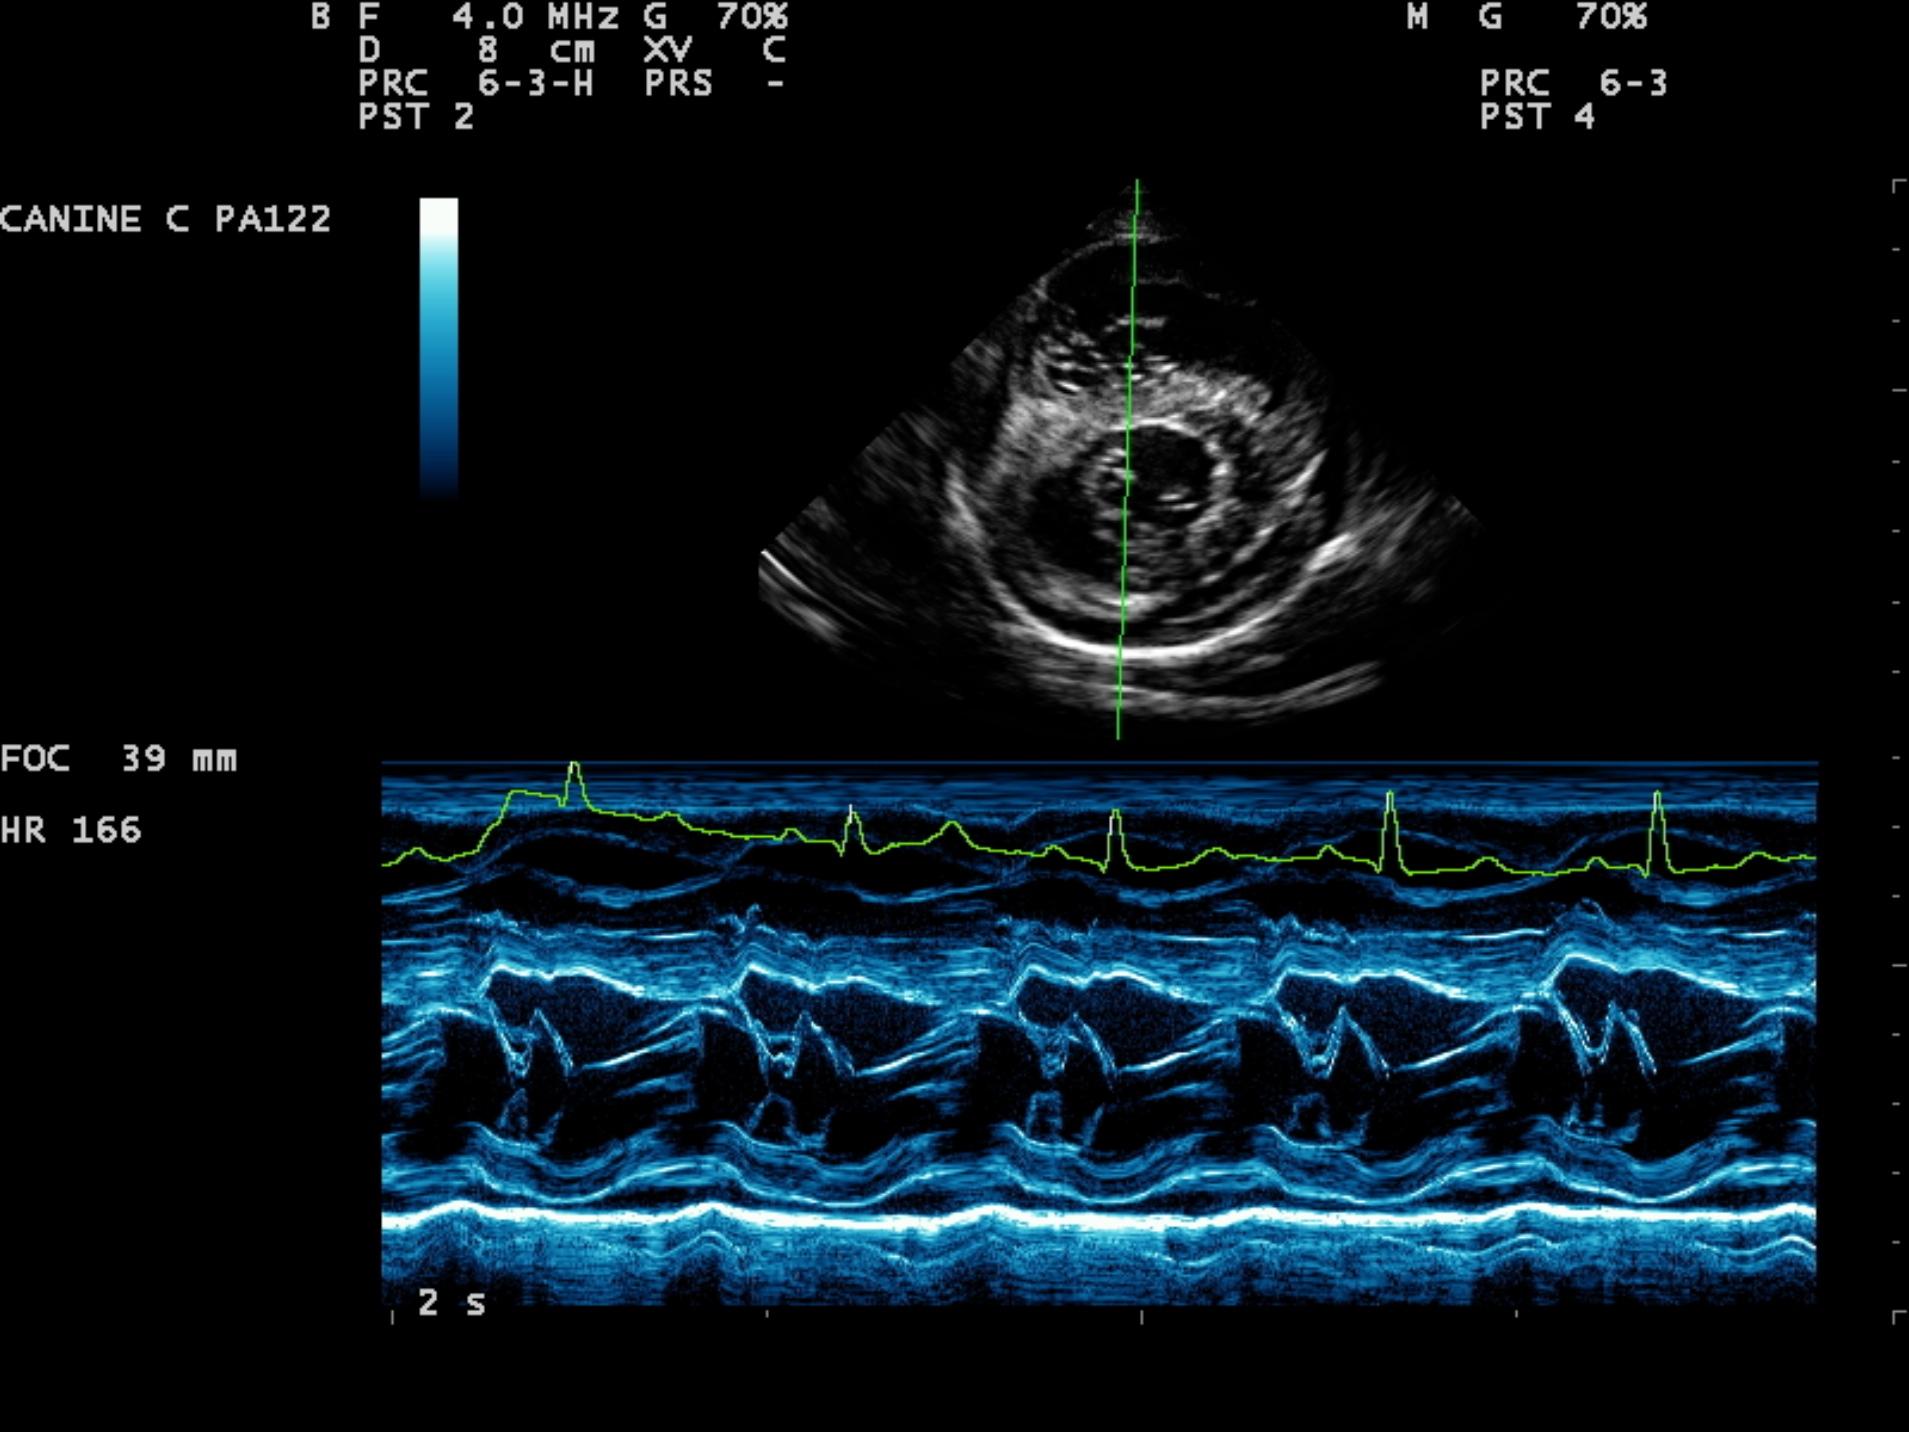

An 8-year-old F Maltese was presented for examination. A grade 5/6 systolic heart murmur was noted. Radiographs revealed severe generalized cardiomegaly and an unremarkable pulmonary parenchyma. Moderate hepatomegaly and ascites was additionally noted.